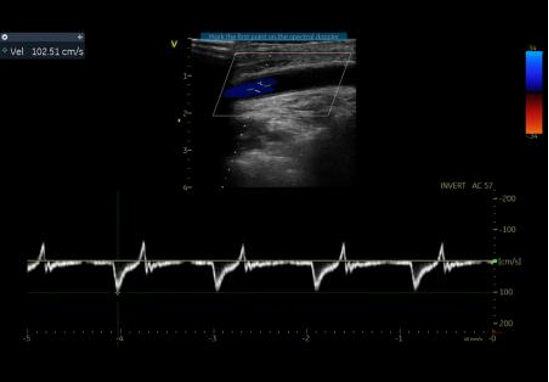

通过右肱动脉置入球囊,术中制造临时性Ⅰ型内漏,实现头臂干血流70%、左颈总动脉60%、左锁骨下动脉40%-50%的维持。